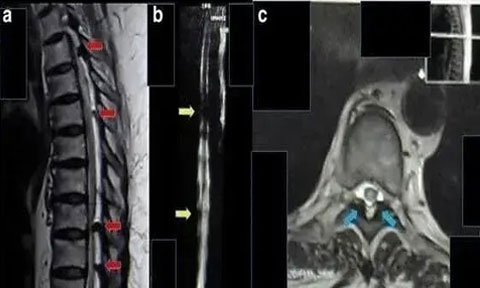

2017 年海外報道一例 62 歲的印尼籍婦女,被診斷為胸部截癱、慢性腎功能衰竭、糖尿病,慢性腎功能衰竭 2 年,肌酐水平為 11 mg/dL,無小便。采用間充質干細胞移植方案治療,鞘內注射和靜脈注射后三周后,患者可以移動腳趾,腎功能得到改善。肌酐水平降至 9 mg/dL。8 個月后,患者可以抬起腿,肌酐水平是 2mg/dL,小便恢復正常。